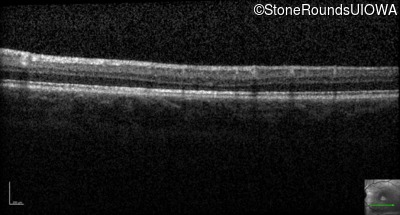

Optical Coherence Tomography - Right - 20/40 -2

Exemplar / OCT Stack